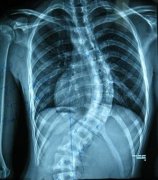

强直性脊柱炎是一种慢性进行性疾病,主要表现为椎间盘纤维,及其 ...